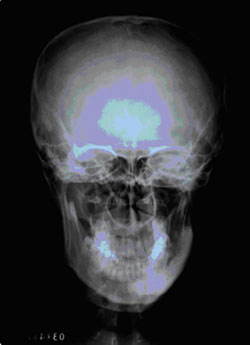

头颅X光片 正侧位,仰头位或是其它特殊位置

图6 头颅正位平片

(来自解剖学图谱)